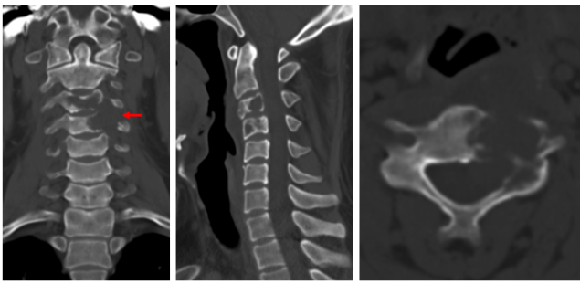

经过查看外院影像学检查,发现其“C3-4椎体破坏性病变,椎管内外哑铃形占位,脊髓受压”,基本符合神经鞘瘤诊断,而韦峰却坚持让小石先去放射科做CT引导下穿刺活检,进行“金标准”的确认。

图1 影像学检查

“脊椎肿瘤手术机会特别少,不同肿瘤切除方式各异,不能冒然切除。”脊柱原发肿瘤发生率较低,但类型多样,影像学诊断准确率不足60%,存在着“同征异病,同病异征”的问题。韦峰认为,神经鞘瘤为良性肿瘤,通常进展缓慢,短时间不会造成神经损伤,手术相对简单。如果万一是恶性肿瘤而按照神经鞘瘤的切除方式手术,必然会造成肿瘤复发。医生的坚持说服了小石。